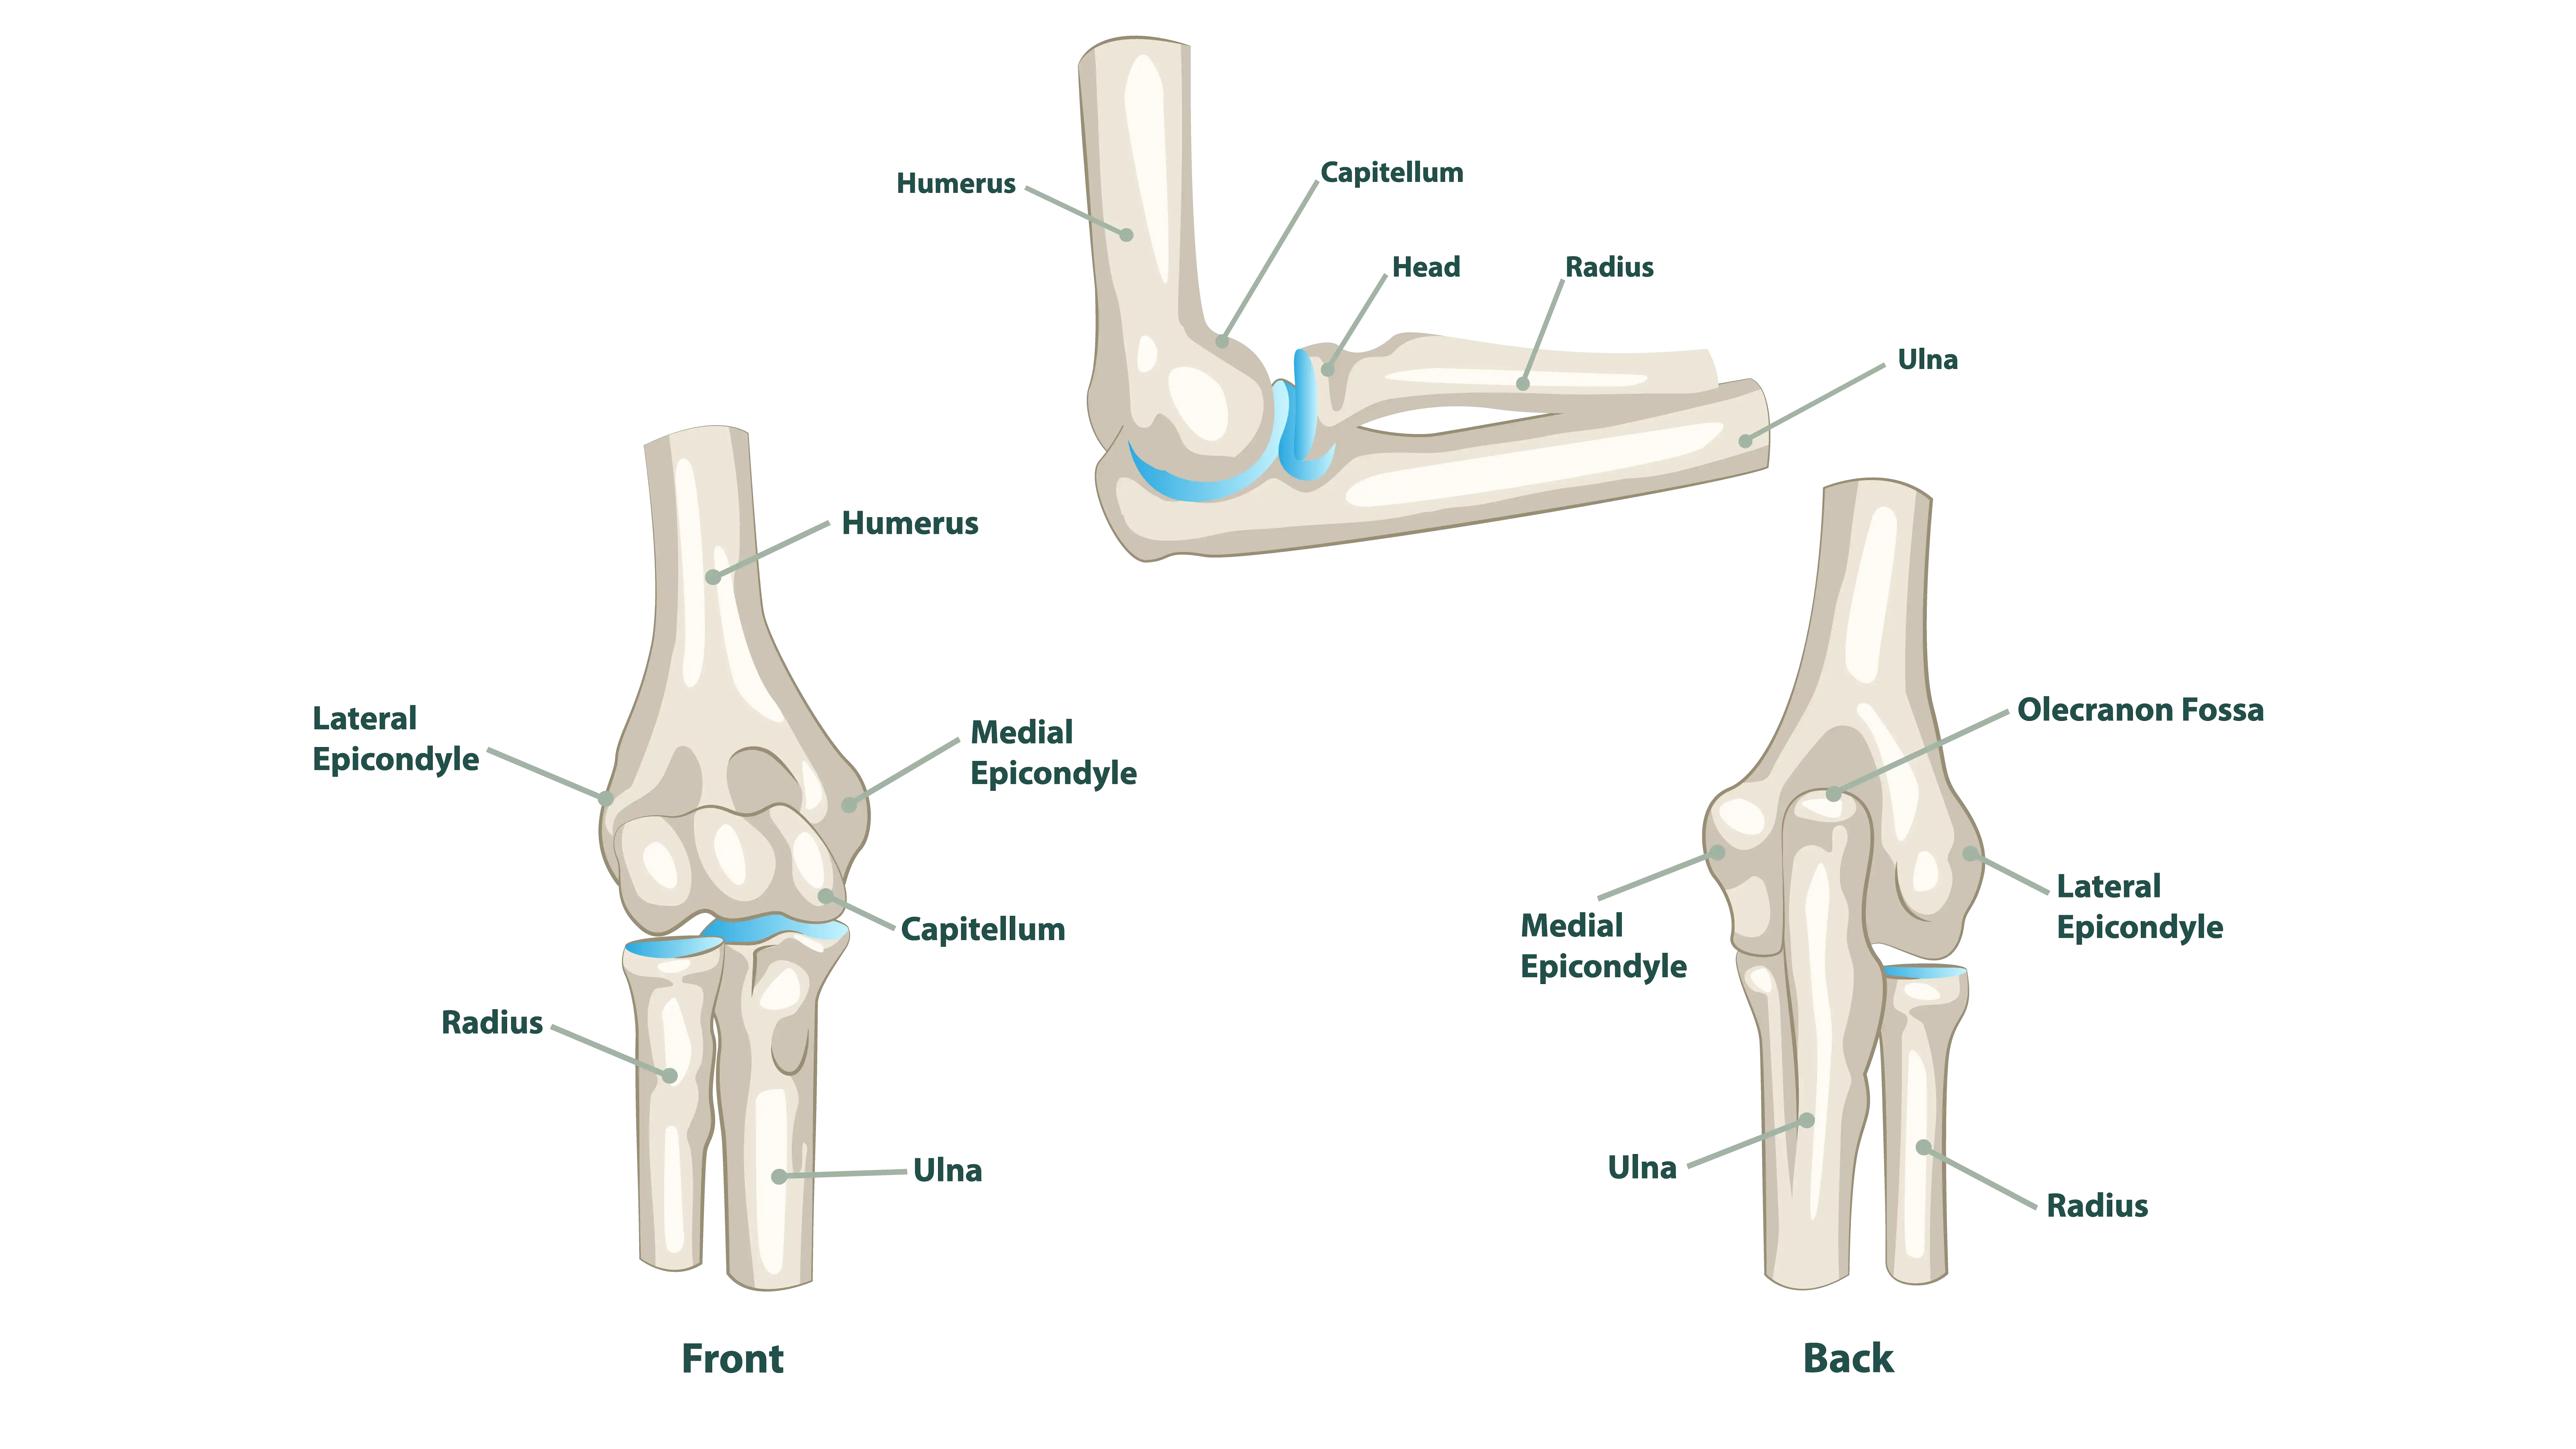

Anatomy of the Elbow

The elbow is formed by the articulation of the humerus, radius, and ulna. Stability comes from strong ligaments, including the ulnar and radial collateral ligaments, while muscles and tendons crossing the joint provide movement and power. Because of its complex structure, the elbow is prone to both acute injuries and chronic overuse disorders.

This condition occurs when repetitive gripping or wrist extension leads to microtearing of the tendon that attaches to the lateral epicondyle. Patients usually develop pain on the outer side of the elbow, worsened by lifting or gripping.